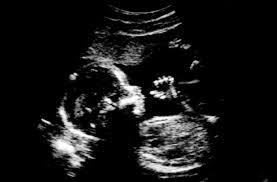

You are pregnant. The day you’ve waited for(or maybe not….suprise!) since you were a little girl: becoming a mommy. Thousands of hours are spent day dreaming about the day you’re little girl or guy gets here. What color hair they’ll have, how big will they be, and for some is it a boy or girl, but often very little though is given to the reality of acutallly delivery a baby.